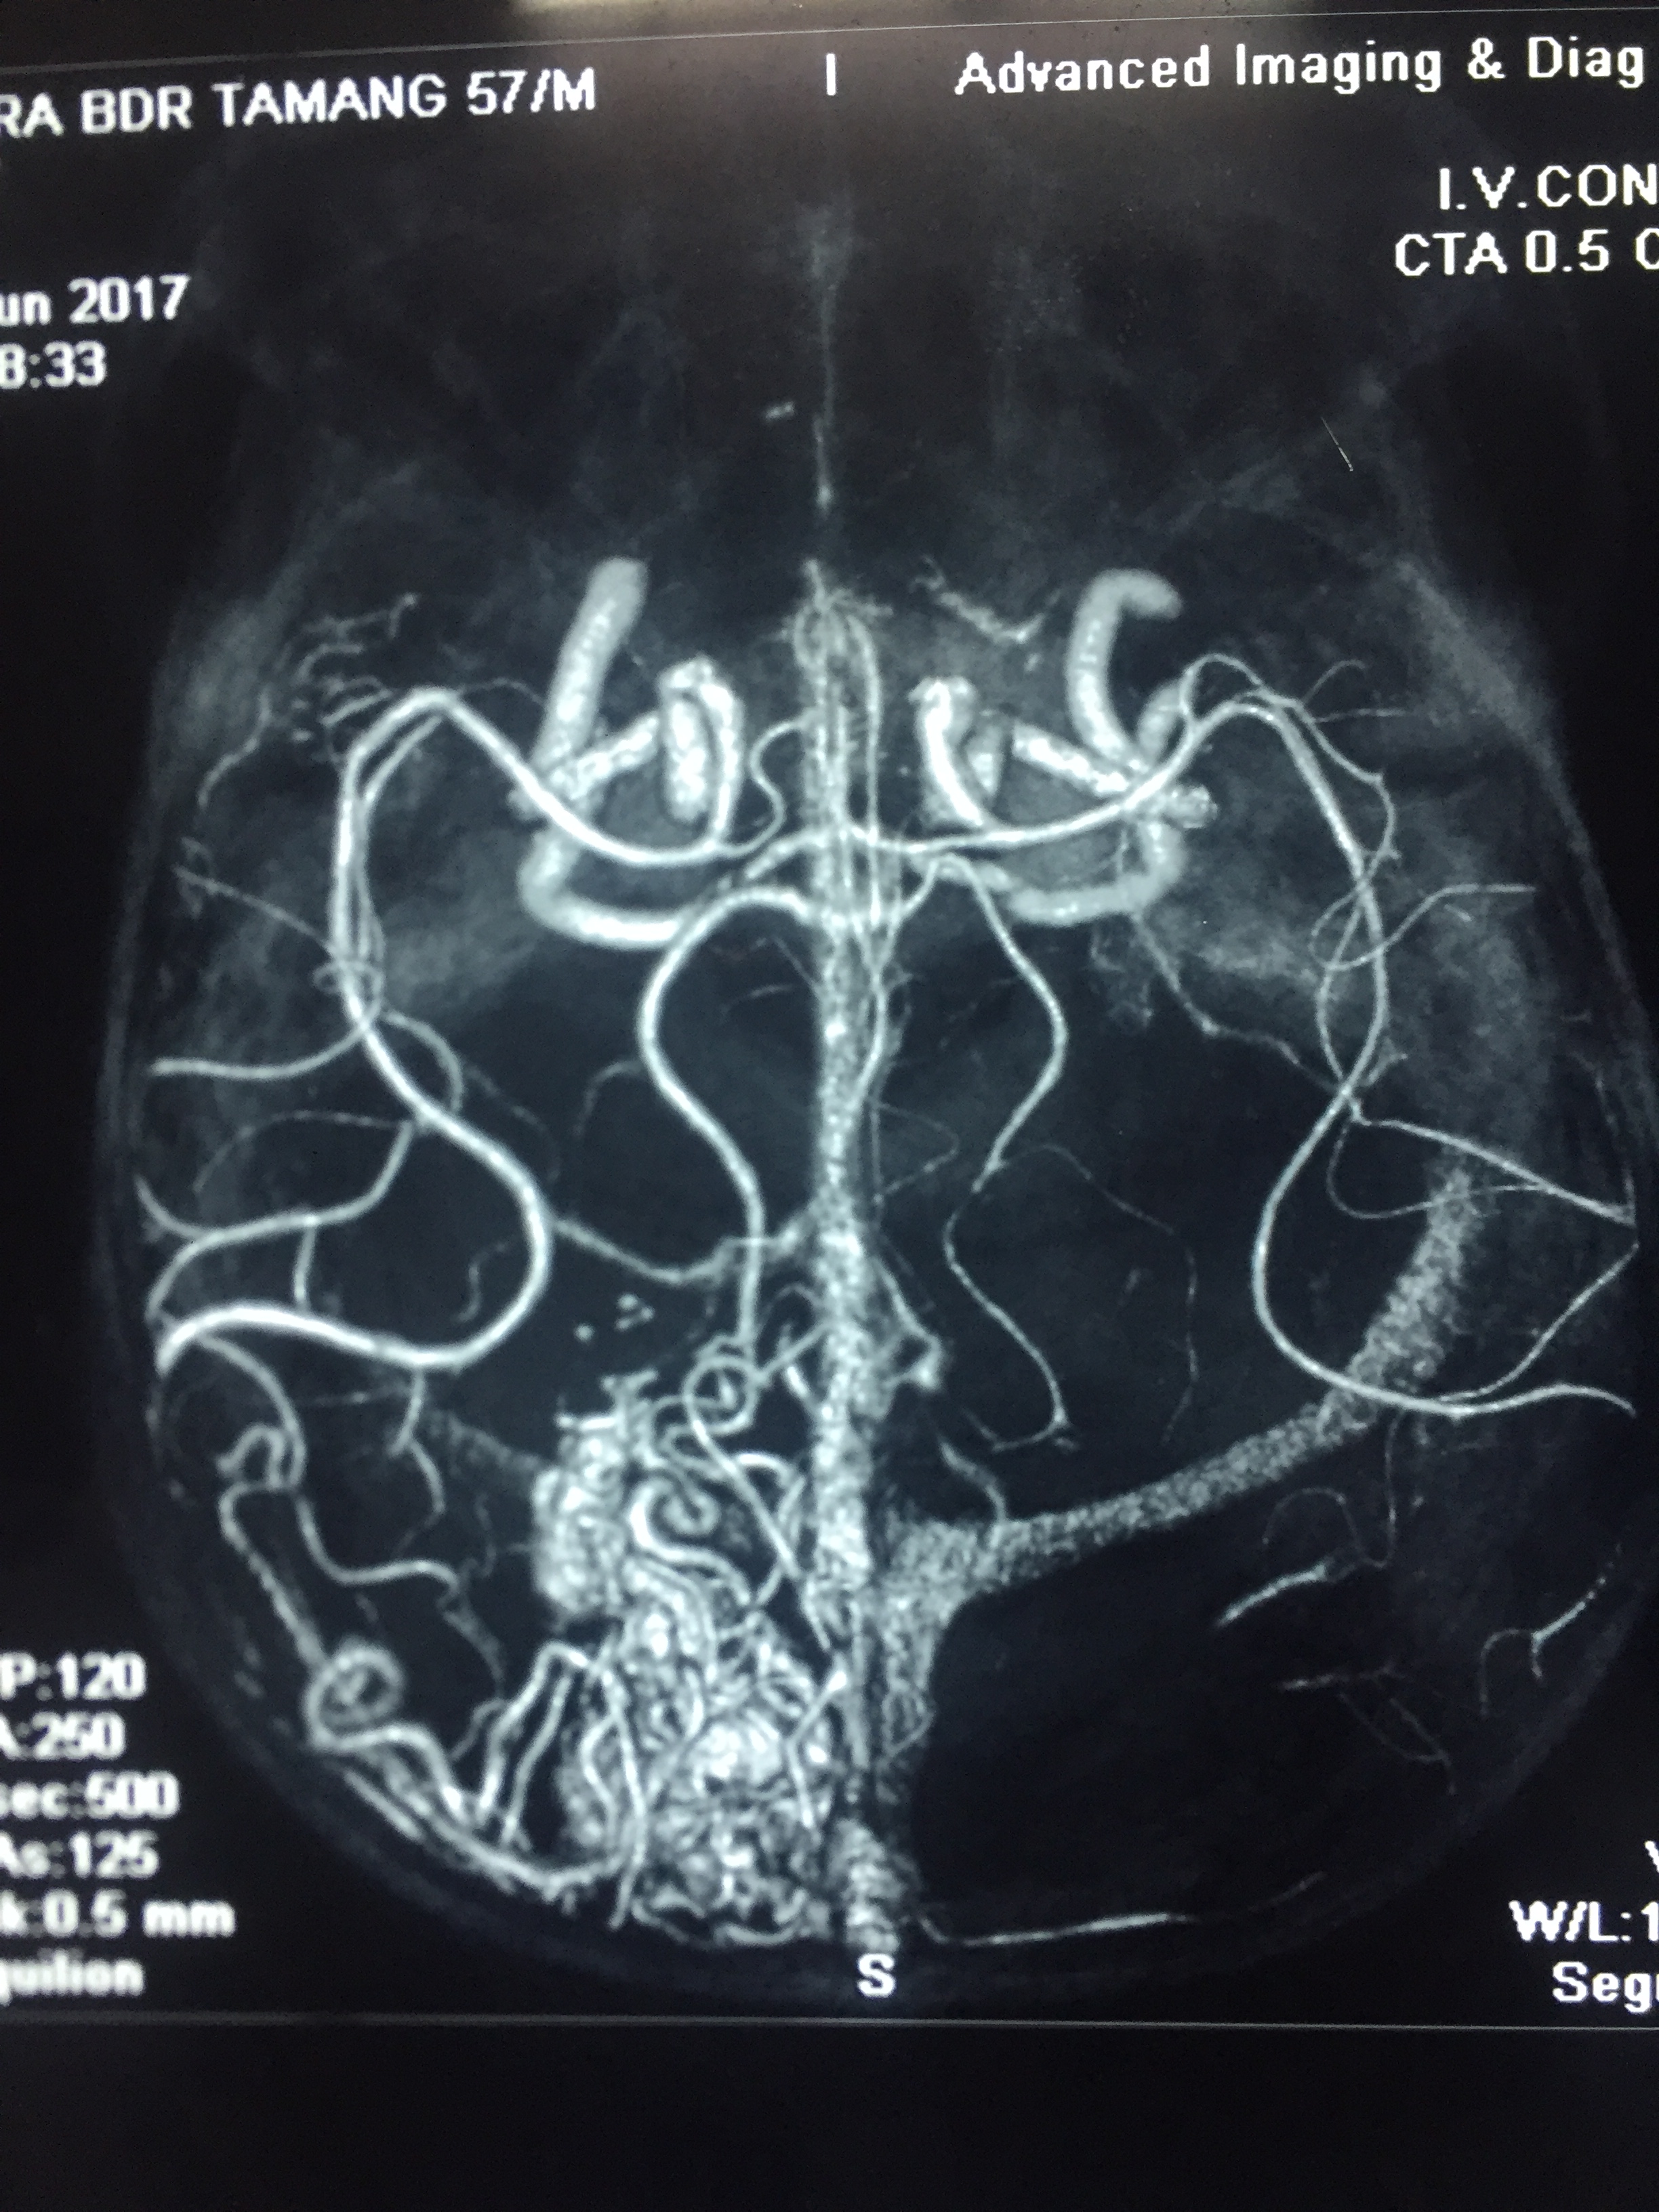

Post Traumatic Carotid Cavernous Fistula ( CCF ) : Sugery - Transcarnial Transcavarnous Oclusion of Fistula